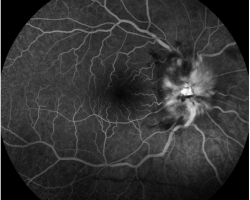

- Angiographie fluorescéine : papillite à droite, normal à gauche

- Angiographie fluorescéinique, OCT et périmétrie cinétique (cf. supra). Pour information : pas de déficit de l’OCT RNFL à gauche (non interprétable à droite du fait de l’œdème papillaire). Pas de déficit de la couche des cellules ganglionnaires à gauche (liée probablement à une poussée de névrite gauche ancienne ou présence de lésion démyélinisante en rétrochiasmatique vu la congruence du déficit du champ visuel des deux yeux).